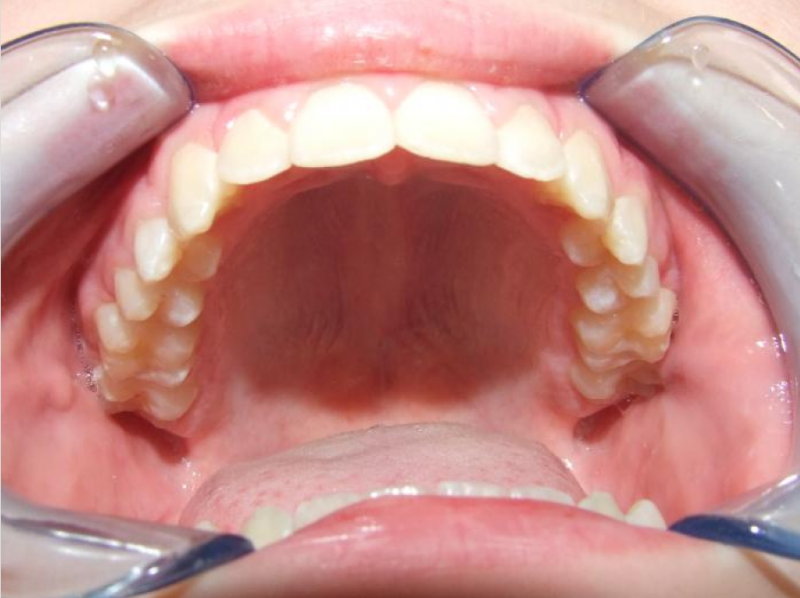

eindfoto

Beschrijving

Leeftijd bij aanvang: 10 jaar

Bonded Hyrax + volledig vast onderkaak

Volledig vast bovenkaak + expander

Wrap + c-c bar onderkaak

Leeftijd bij afname: 12 jaar